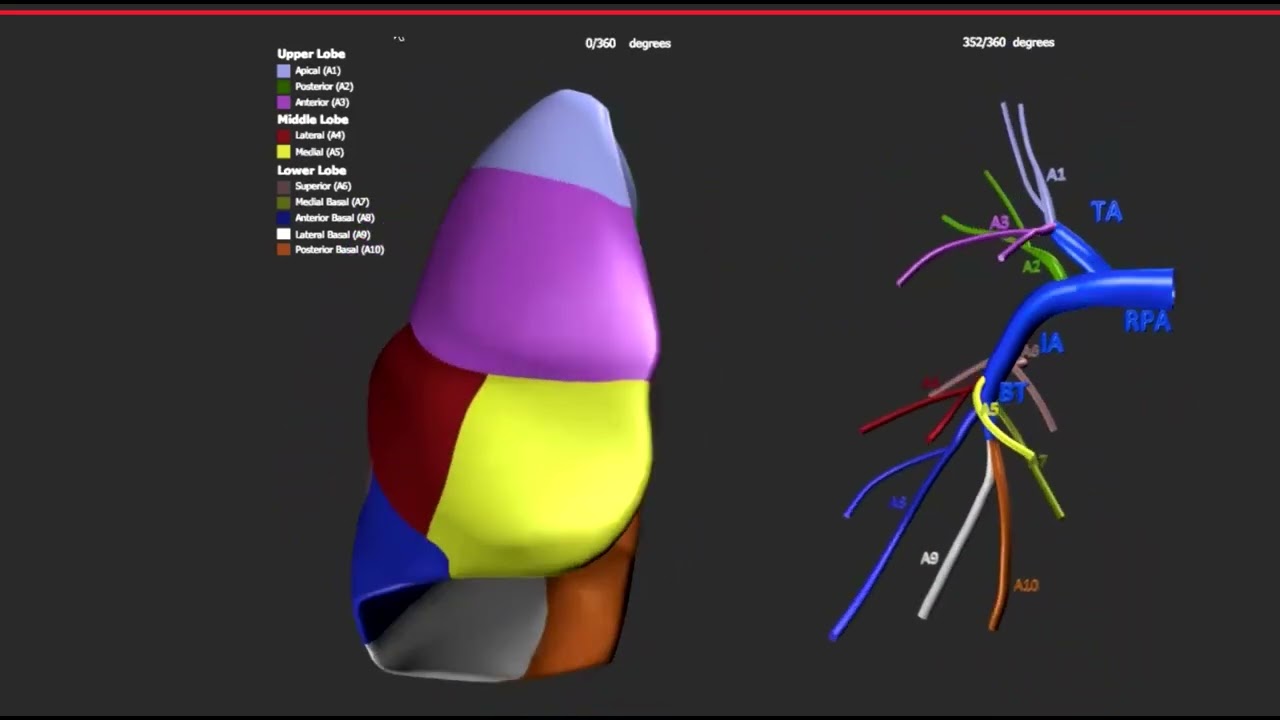

Dr. Hady Lichaa continues his discussion with Dr. Nyal Borges on the use of microcatheters in interventional cardiology.

Dr. Hady Lichaa speaks with Dr. Nyal Borges about microcatheters, and why there are essential in interventional cardiology.

In this episode of Practice Tips, Dr. Hady Lichaa outlines the balloon puncture access technique, which is applicable to ...

In this edition of Dr. Hady Lichaa's Practice Tips series, Dr. Lichaa expands on a previous video by detailing the use ...

In this edition of Dr. Hady Lichaa's Practice Tips series, Dr. Lichaa addresses the interventional aspects of Balloon ...

In this edition of Dr. Hady Lichaa's Practice Tips series, Dr. Lichaa details the role of angulated micro-catheters in ...